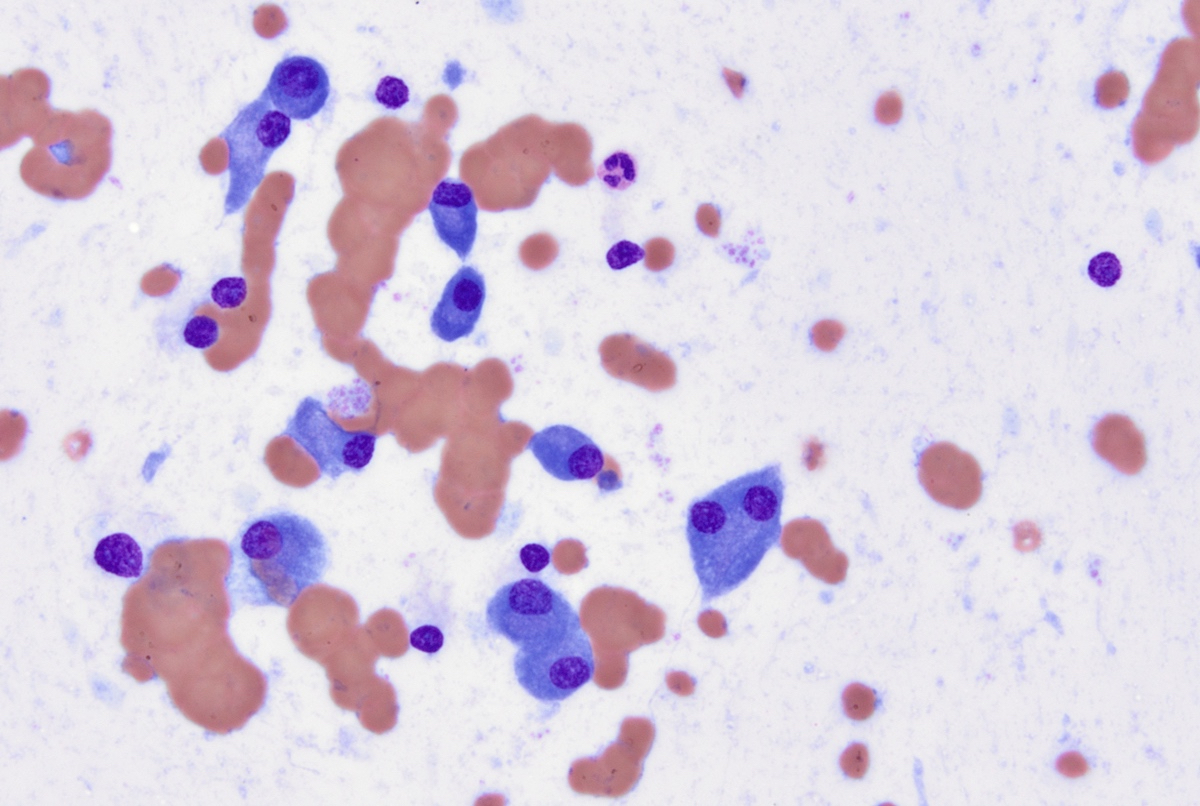

Cytology description

- Cytology can assess plasma cell morphology (e.g., mature, immature, plasmablastic) but number of plasma cells present may vary substantially from the core biopsy

- Mature plasma cells: oval with abundant basophilic cytoplasm, perinuclear hof, round eccentric nuclei, clock face chromatin and indiscernible nucleoli

- Immature plasma cells: higher nuclear to cytoplasmic ratio, more abundant cytoplasm and hof region compared to plasmablastic, more dispersed chromatin, often prominent nucleoli

- Plasmablastic: less abundant cytoplasm with little or no hof region, fine reticular chromatin, large nucleus (> 10 microns) or large nucleolus (> 2 microns) (Blood 1998;91:2501)

- Pleomorphic: multinucleated, polylobated

- Rare cases may have small, lymphoid appearing plasma cells or plasma cells with marked nuclear lobation

- Immature or pleomorphic features are rare in reactive plasma cell proliferations

- Morphologic features:

- Mott cells / morula cells: multiple grape-like cytoplasmic inclusions comprised of crystalized immunoglobulin

- Russell bodies: hyaline intracytoplasmic inclusions

- Flame cells: vermillion staining glycogen rich IgA in cytoplasmic projections (American Society of Hematology: Flame Cells in Multiple Myeloma [Accessed 26 May 2022])

- Pseudo-Gaucher cells / thesaurocytes: overstuffed fibrils (J Clin Pathol 1976;29:916)

- Cytoplasmic crystals: occasional in myeloma, common in adult Fanconi syndrome (Am J Clin Pathol 1983;80:224)

- Dutcher body: pale staining immunoglobulin filled cytoplasm invaginating into the nucleus and appearing as an intranuclear inclusion, single and usually large, more common in IgA myeloma